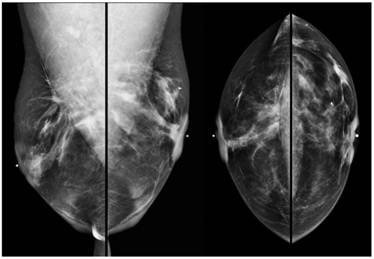

Screening MRI of both breasts performed 15 months later demonstrated interval development of a 1.1 cm enhancing ill-defined mass at the 1 o'clock axis of the left breast (Figure 1). A corresponding solid hypoechoic mass with angulated margins was seen on targeted left breast ultrasound (Figure 2). Mammography demonstrated heterogeneously dense breast tissue with post surgical changes bilaterally. No dominant mass or suspicious clustered microcalcifications were identified in either breast (Figure 3). Ultrasound guided core biopsy yielded moderately differentiated invasive ductal carcinoma.

Figure 3

Digital bilateral mammogram demonstrating heterogeneously dense breast tissue and post surgical changes bilaterally. A microclip is seen at the 1 o'clock axis of the left breast, marking the site of ultrasound guided core biopsy.